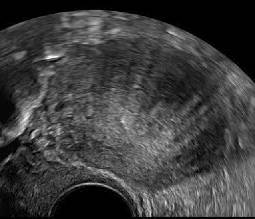

Abb. 7

Ein Nebeneinander von hyper- und hypoechogenen Inseln im Myometrium